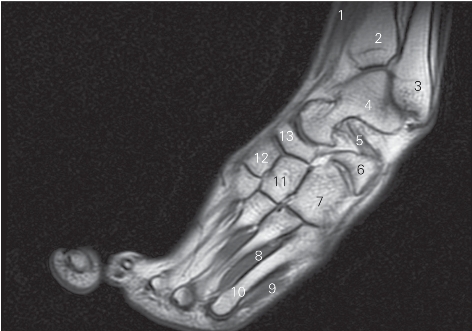

图5-62 经第二跖骨的足冠状断层MR T1加权图像

1 胫骨前肌 tibialis anterior 2 胫骨 tibia

3 腓骨长短肌 peroneus longus and brevis 4 跟骨 calcaneus

5 外侧楔骨 lateral cuneiform bone 6 骰骨 cuboid bone

7 小趾展肌 abductor digiti minimi

8 小趾短屈肌 flexor digiti minimi brevis 9 骨间肌 interossei

10 第二跖骨 2ed metatarsal bone

11 内侧楔骨 medial cuneiform bone 12 足舟骨 navicular bone

13

长伸肌腱tendon of extensor hallucis longus 14 距骨 talus

图5-63 经第五跖骨的足冠状断层MR T1加权图像

1

长屈肌 flexor hallucis longus 2 胫骨 tibia

3 外踝 lateral condyle 4 距骨 talus

5 跗骨窦 sinus tarsi 6 跟骨 calcaneus

7 骰骨 cuboid bone 8 骨间肌 interossei

9 小趾展肌 abductor digiti minimi 10 第五跖骨 5th metatarsal bone

11 外侧楔骨 lateral cuneiform bone

12 中间楔骨 intermediata cuneiform bone

13 舟骨 navicular bone